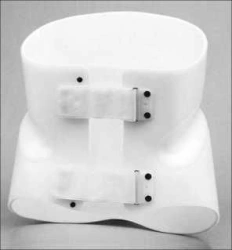

Custom Rigid Support Corset for Enhanced Stability

US$90-360

Weight:

2.2

Plastic color:

white

ORTOSTAN LLC 🇷🇺

Rigid Corset for Sitting Position Stabilization KRO-235

US$180-720

Material:

Polymer

Material:

Polymer

MOSCOW PROP OJSC 🇷🇺

Rigid Thermoplastic Corset KR0-234

US$90-360

Material:

Polymer

Material:

Polymer

MOSCOW PROP OJSC 🇷🇺